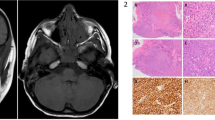

A total of 84 patients were included in this research, with a mean age of 62.24 ± 14.52 years and male-to-female ratio of 43:41. The pathological types comprised benign orbital lymphoproliferative tumours (26/84, 31%, mean age 59.31 ± 10.4 years, male-to-female ratio of 16:10) and malignant orbital lymphomas (58/84, 69%, mean age 63.55 ± 15.93 years, male-to-female ratio of 27:31). The most common symptoms in benign and malignant OLPDs were palpable mass and eyelid swelling. Typically, malignant orbital lymphoma masses exhibited low signal intensity on T1-weighted imaging (T1WI), whereas benign lymphoproliferative tumours commonly demonstrated iso-intensity on T1WI. Notably, the expression of cluster of differentiation 3, 5, 10, 23, 43, and human immunoglobulin light chain lambda demonstrated statistically significant differences between the benign and malignant OLPD groups.